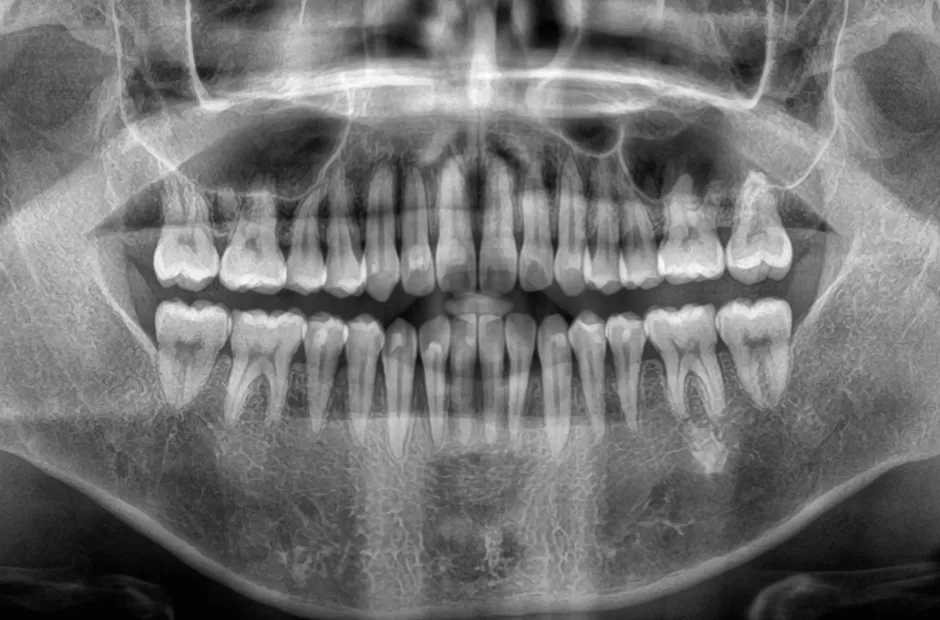

過剰歯

| 診断名・主訴 | でこぼこ |

|---|---|

| 年齢・性別 | 22歳・女性 |

| 治療期間・回数 | 1年6か月 |

| 治療に用いた主な装置 | リンガルブラケット |

| 抜歯部位 | 過剰歯 |

| 治療費 | 100万円(税抜) |

| リスク・副作用 | 装置による違和感・疼痛・歯肉退縮・歯根吸収・虫歯のリスクなど |

治療後